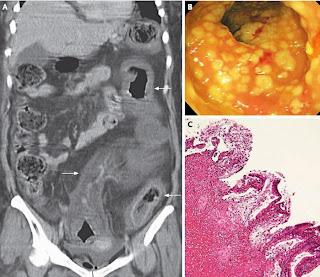

C. difficile colonizza il colon e rilascia due tossine (chiamate TcdA e TcdB) che generano colite nelle persone suscettibili, disattivando alcune GTPasi della famiglia Rho, che portano alla morte delle cellule intestinali, perdita della funzione di barriera ed aumento di infiammazione colica; l’infezione é trasmessa da spore che sono resistenti al caldo, gli acidi ed agli antibiotici e che sono distribuite in gran parte nei terreni ed in piccola quota sulle superfici, sia comunitarie che nosocomiali. La colonizzazione intestinale é prevenuta dalle proprietà del microbioma intestinale, che viene danneggiato dall’utilizzo di antibiotici in grado di eliminare gran parte della flora intestinale; anche l’età avanzata, la chemioterapia e le malattie croniche debilitanti contribuiscono ad aumentarne la suscettibilità. Le manifestazioni cliniche non sono sempre evidenti.